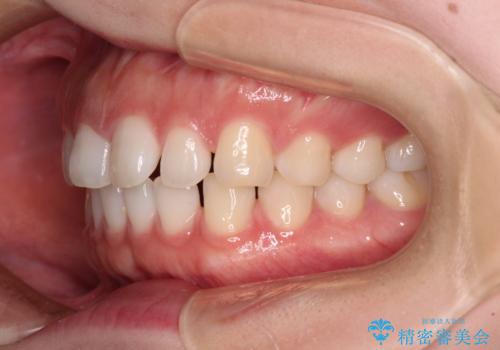

すきっ歯とオープンバイト インビザライン・ライトで改善

- 食いしばりによる顎の負担を気にして来院された患者様です。

当初は、ボツリヌス毒素による咬筋の過緊張の緩和と、睡眠時のマウスピース装着による咬合負担の解消を行いました。

オープンバイトのため、奥歯に負担のかかる咬合状態であったので、矯正治療を提案したところ、希望をされました。

すきっ歯程度の軽度の歯列不正であったため、インビザライン・ライトにより咬合改善を行うこととしました。

オープンバイトやすきっ歯は、舌突出癖によりあっという間に後戻りをするため、矯正治療前からトレーニングを行っていただき、更には後戻り防止のワイヤーリテーナーを併用しています。